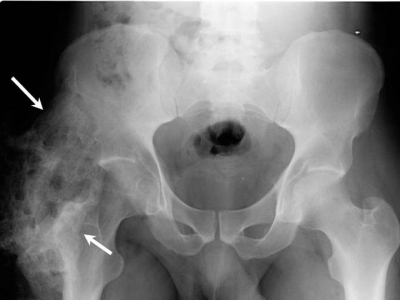

- Tai nạn giao thông cách đây 4 năm, bệnh nhân bị chấn thương sọ não, gãy xương chày, mác trái và gãy xương mặt.

- Phẫu thuật nẹp vít xương chày và xương mác trái sau tai nạn giao thông